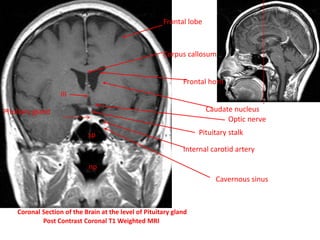

Coronal Section of the Brain at the level of Pituitary gland

Post Contrast Coronal T1 Weighted MRI

sp

np

Frontal lobe

Corpus callosum

Frontal horn

Caudate nucleus

III

Pituitary stalk

Pituitary gland

Optic nerve

Internal carotid artery

Cavernous sinus